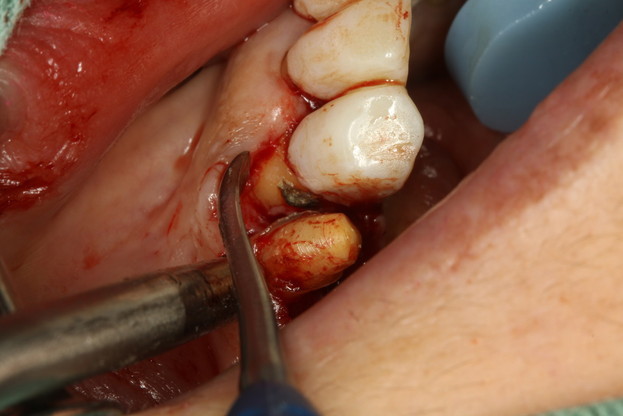

歯を抜きたくない方のための骨の再生治療

歯を抜くあるいは抜けてしまう原因で今一番多いのが歯周病によるものです. 歯周病にかかって歯の周囲を支える骨が無くなってしまうと歯が揺れてしまい、歯茎の内部に細菌が侵入してしまって炎症が歯茎の内部深くでおこります.歯の周囲の骨のほとんどが吸収してしまった場合は歯を抜かなくては行けない場合もあります.